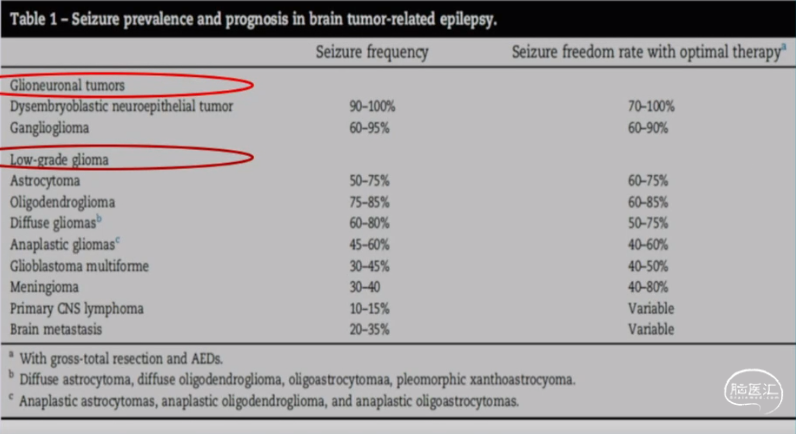

生长缓慢的肿瘤更容易有癫痫,特别是神经胶质发育性肿瘤(Neuroglial developmental tumors)

•癫痫是脑膜瘤最常见的术前症状之一,占30%-40%

•术后癫痫无发作60%-80%

•术前发生率30%-60%

•术后癫痫无发作40%-80%

•发生率60%-75%

•术后癫痫无发作65-80%

•癫痫发生率90%-100%

•术后癫痫无发作70-90%